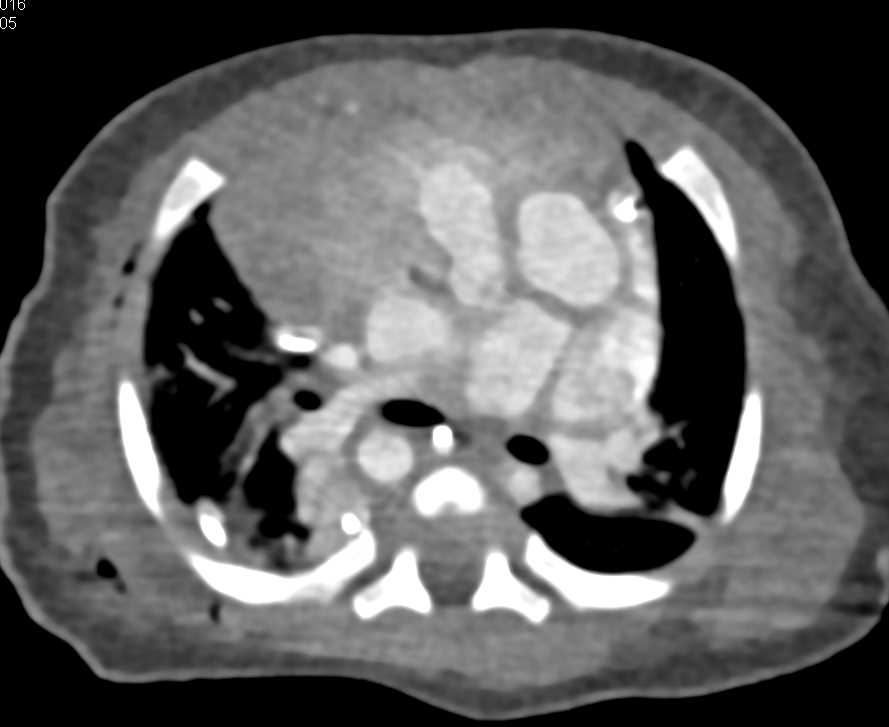

Thymus in Child Chest Case Studies CTisus CT Scanning Thymus X Ray Baby The embryology and anatomy of the thymus, its normal variations and ectopic locations, dynamic changes in the thymus, and various thymic disorders are discussed, with emphasis on differentiating benign and malignant processes to avoid unnecessary invasive procedures. In infants and young children, the thymus can be impressively large on frontal radiographs. The aim of this article is to review the. Thymus X Ray Baby.